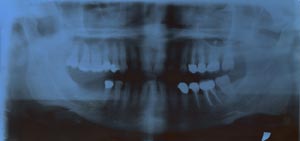

CASO INIZIALE

Radiografia panoramica